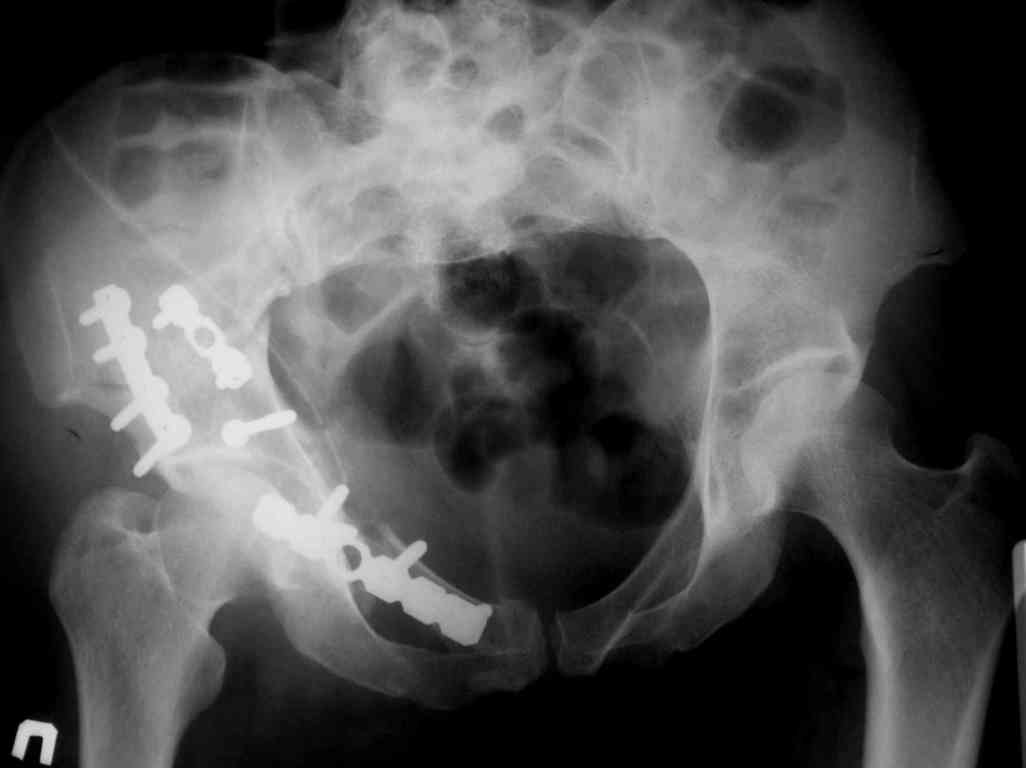

Дальше как обычно: рекон пластнина на заднюю колонну. Устранить смещение передней колонны из заднего доступа оказалось невозможным, пришлось

перевернуть больную на спину и из подвздошного доступа вернуть переднюю колонну на место. Другая проблема возникла с фиксацией лонной кости,

пришлось открывать ся над лобком и ретроградно двумя винтами фиксировать обе ветви лобковой кости справа и слева.

Пока всё ОК снимки сделали сегодня, но пока не сфотографировал В целом суставная поверхность конгруэнтна , по колоннам тоже вроде все ОК.

Интраопер под ЭОПом контролировал направление лонного винта - была абсолютная уверенность в правидльности направл, на постоп. снимке винт вылез :-((.